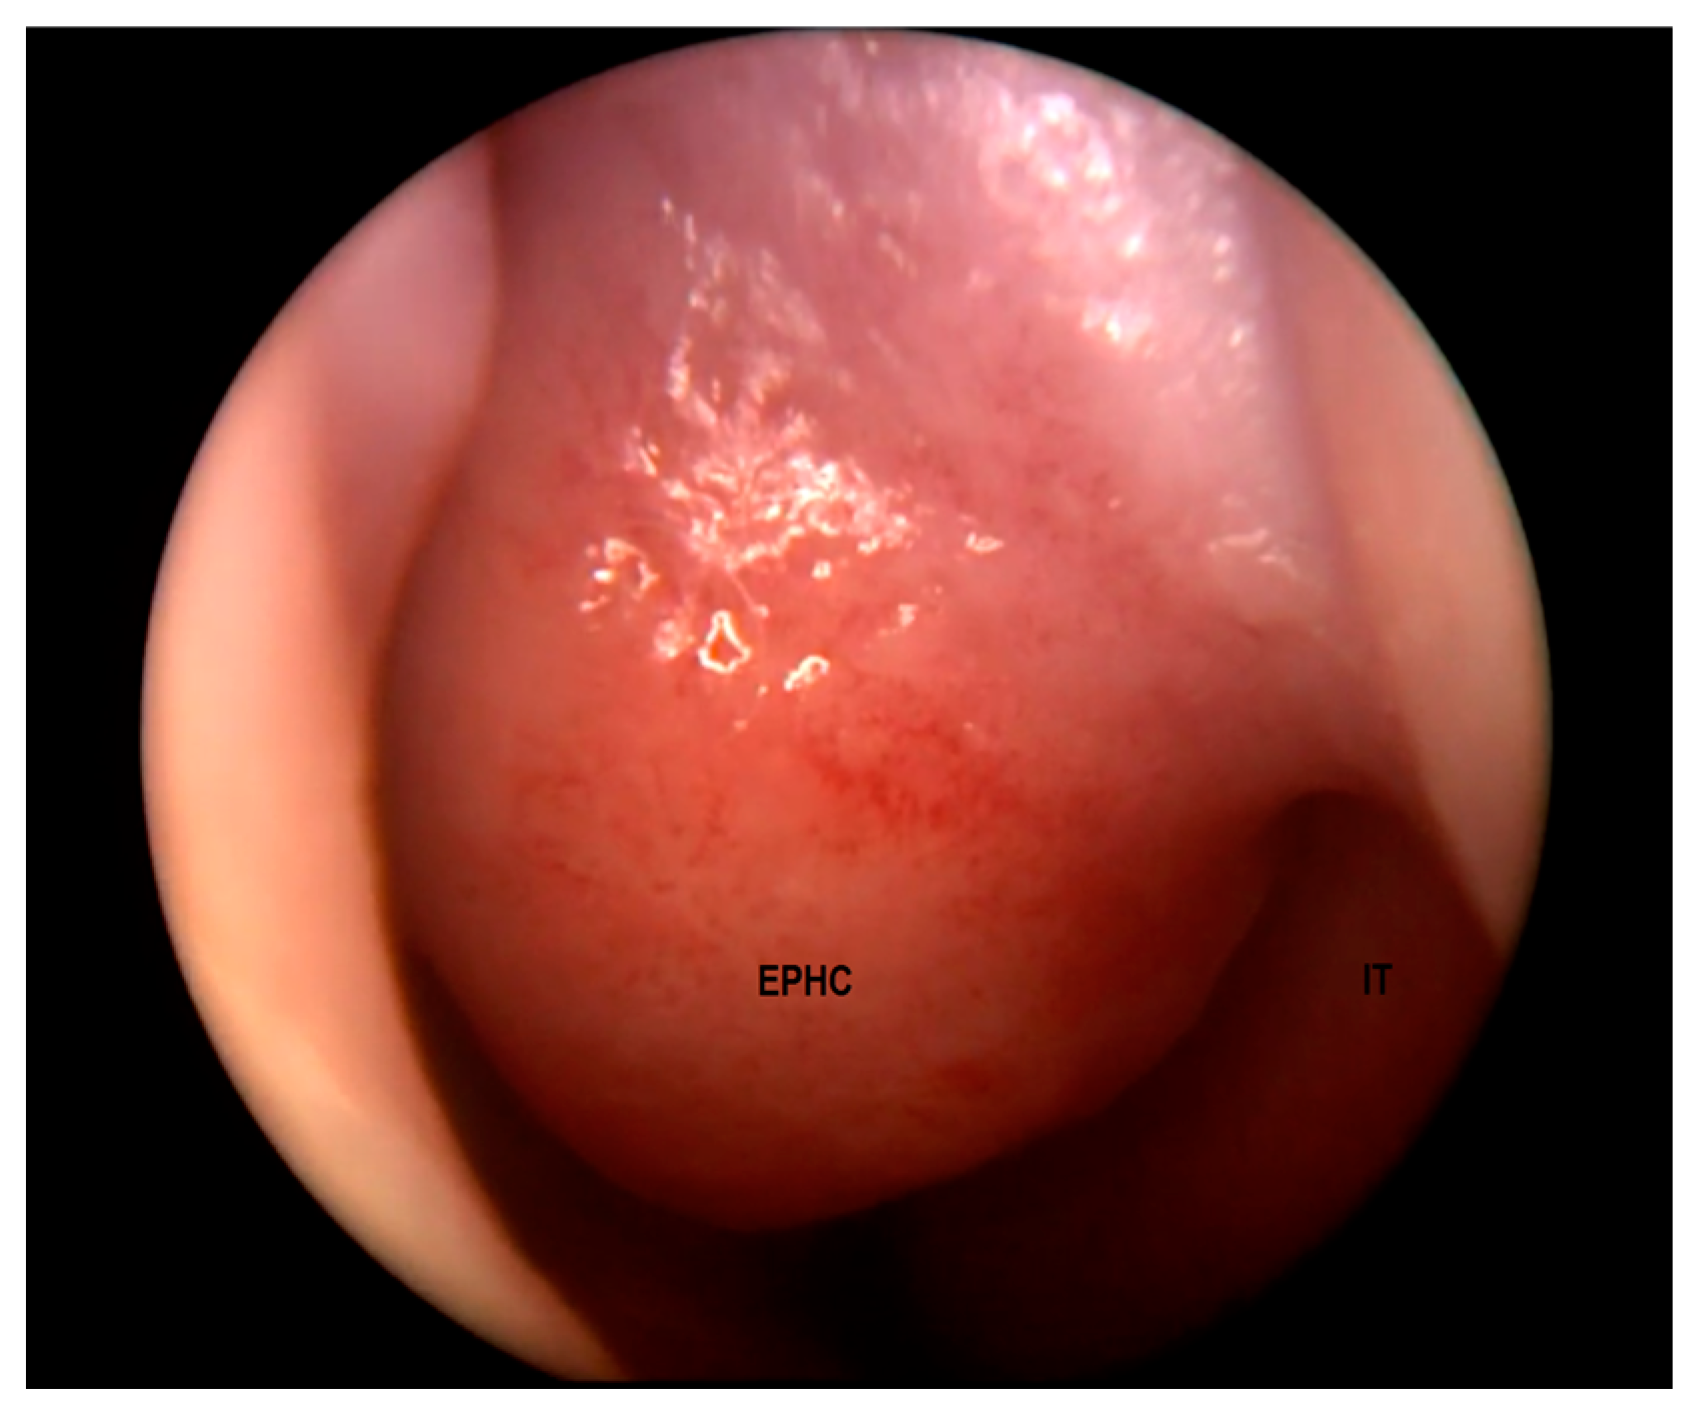

| Characteristics | Hair visible in the skin ostium; non-expansile, non-pulsatile, non-compressible, and non-transilluminating mass | Tends to grow along with the patient; firm and non-compressible mass, non-transilluminating; intranasal—pale, “polypoid”; extranasal—smooth, well-circumscribed, reddish or bluish, often with telangiectasis on its surface | Smooth “polypoid” mass, pink or bluish, covered with mucous membrane, usually pulsatile, transilluminating, soft, and compressible | |